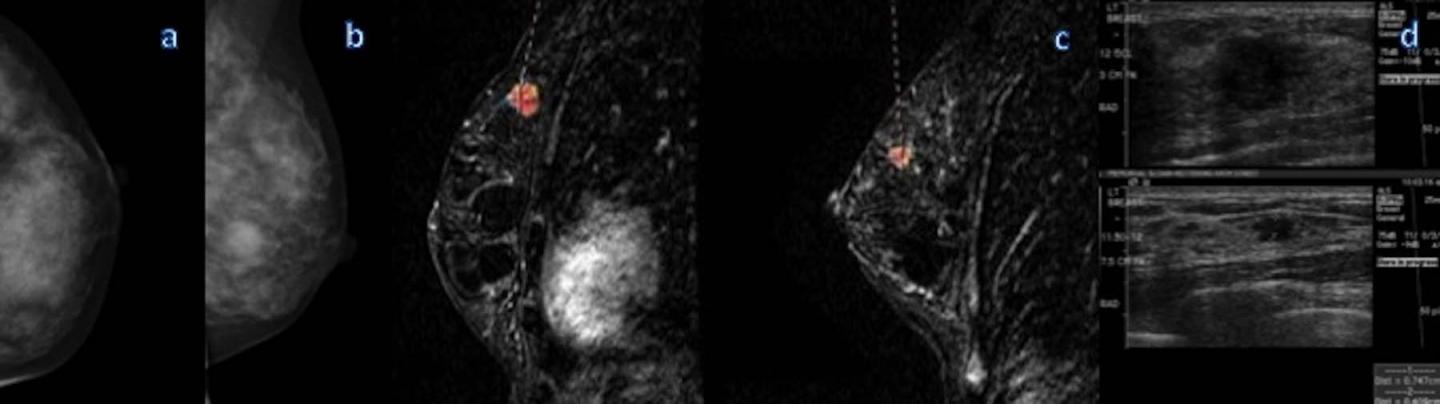

OAK BROOK, Ill. - Additional breast cancers found with MRI are sometimes larger and potentially more aggressive than those found on mammography, according to a study published online in the journal Radiology . Researchers said that in some cases MRI findings of additional cancers not seen on mammography may necessitate a change in treatment.

Breast MRI is the most sensitive technique for the detection of breast cancer, with widespread application in the screening of high-risk patients and pre-surgical planning. In younger women and women with dense breasts, MRI is effective in the detection of what are known as multicentric cancers, meaning breast cancers involving two or more distinct primary tumors, usually in different quadrants of the breast. However, there has been some debate about the clinical significance of multicentric cancers found with MRI.

In 73 of those 285 patients, or 25.6 percent, MRI identified at least one additional cancer in a different quadrant of the breast than the index cancer, or the cancer detected by mammography and/or breast palpation.

These multicentric cancers were larger than the known index cancer in 17 of the 73 patients, or 23.3 percent. In addition, the MRI-detected multicentric cancers were greater than 1 centimeter in size in 25 percent of the 73 patients.

"We believe invasive cancer larger than 1 centimeter is clinically relevant disease," Dr. Iacconi said. "In general, it is accepted that radiation can likely treat invasive cancer less than 1 centimeter, but lesions larger than 1 centimeter, especially invasive carcinomas, may not be reliably treated with conservation."

The additional MRI-detected multicentric cancers were found mostly in patients with heterogeneously dense or extremely dense breasts. However, MRI also detected additional disease in 19 percent of patients with fatty or scattered fibroglandular tissue.

"The results show that multicentric cancer detected on breast MRI after mammography appears to represent a larger tumor burden in approximately a quarter of patients and can result in potential changes to cancer grade and treatment," Dr. Iacconi said.